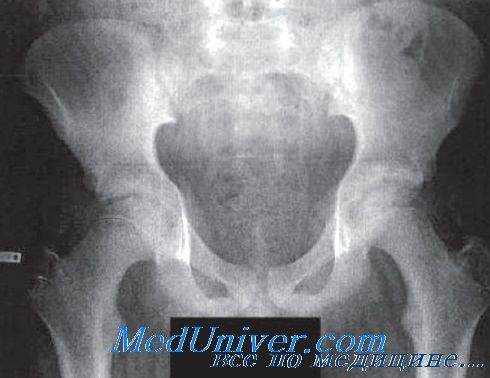

При переломах вертлужной впадины преобладает клиника вывиха бедра (нарушается линия Шемакера, расстояние между вертлюгом и верхней передней подвздошной остью уменьшена). Диагностика переломов таза основывается в основном на данных анамнеза и рентгенологического исследования, локальной болезненности при пальпации, общем состоянии больного.

Существует классификация переломов костей таза:

- травмы тазобедренного кольца без повреждения его непрерывности;

- переломы в месте тазового кольца с присутствием повреждения его непрерывности;

- перелом Мальгеня, при котором характерно двойное вертикальное нарушение костной ткани таза;

- травма в месте вертлужной впадины;

- нарушение целостности тазовых костей совместно с повреждением его внутренних органов.

Выделяют четыре группы переломов костей таза:

- Стабильные (переломы костей таза, не сопровождающиеся нарушением целостности тазового кольца). В эту группу входят изолированные и краевые переломы костей таза.

- Нестабильные (переломы костей таза, сопровождающиеся нарушением целостности тазового кольца). В зависимости от механизма травмы возможно возникновение вертикально нестабильных и вращательно нестабильных переломов. При вертикально нестабильных переломах костей таза целостность тазового кольца, как правило, нарушается в двух местах: в заднем и переднем отделе. Отломки смещаются в вертикальной плоскости. При вращательно (ротационно) нестабильных переломах со смещением смещение отломков происходит в горизонтальной плоскости.

- травмой дна или краев вертлужной впадины, которые в некоторых случаях сочетаются с вывихом бедра;

- переломовывихом тазовых костей, когда происходит также вывих в области лонного или крестцово-подвздошного сочленения.